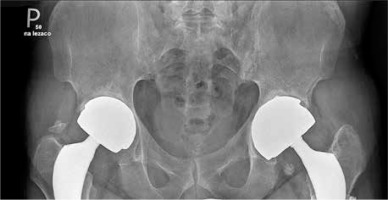

Fig. 1

X-ray of sacroiliac joints showing bilateral ankyloses typical for final stage of ankylosing spondylitis and two hip prostheses. The prostheses were implanted because of severe hip joint destruction caused by ankylosing spondylitis